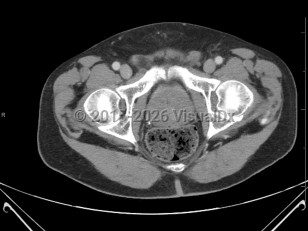

Benign prostatic hyperplasia

Synopsis